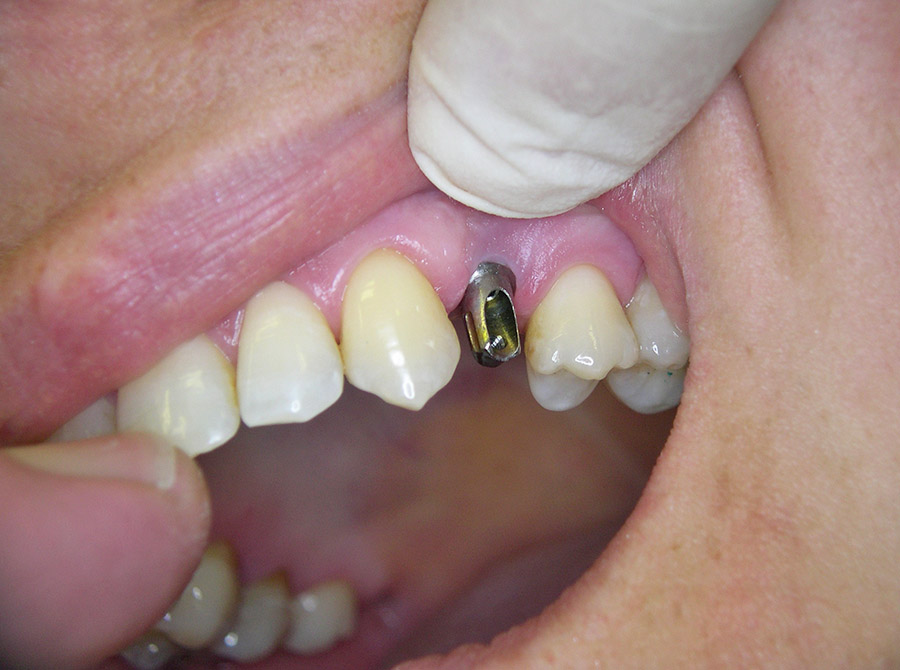

Ein besonderer positiver Effekt der Implantate ist, dass sie den Kieferknochen und das Zahnfleisch erhalten, während sich der Knochen unter Brücken und Prothesen hingegen abbaut. In vielen Fällen lässt sich so die natürliche Rot-Weiß-Ästhetik, also das harmonische Zusammenspiel von Zahnfleisch und Zähnen erhalten, so dass implantat-getragene Kronen kaum von eigenen gesunden Zähnen zu unterscheiden sind.